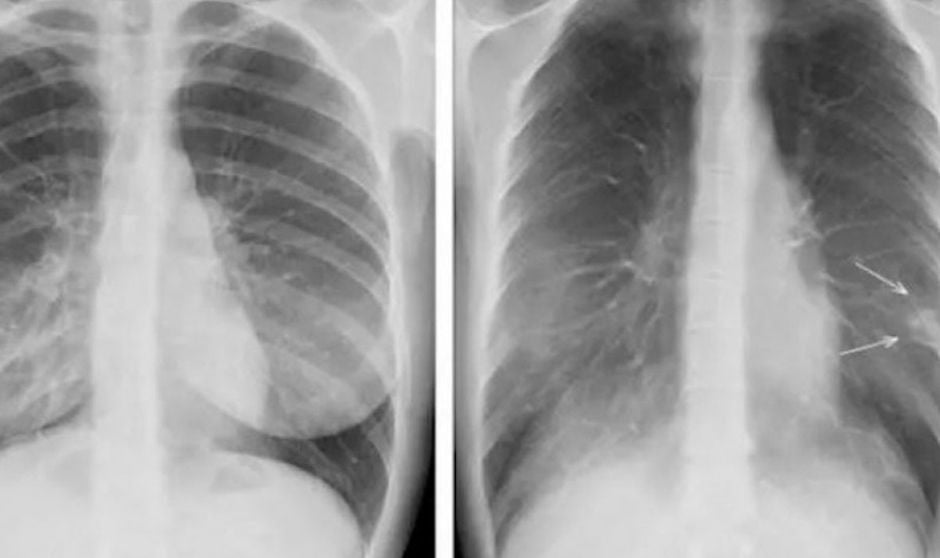

Uso de tomosíntesis en casos Covid-19

Por otra parte, en aquellos momentos críticos, ha comentado García-Santos “empleamos una herramienta intermedia entre el TC y la radiografía de tórax, la tomosíntesis, con una calidad diagnóstica mayor que la de la radiografía, que permitía ver rápidamente una consolidación neumónica, que era el criterio de ingreso.

Más de la mitad de las pruebas que hemos realizado con tomosíntesis de la primera ola venían derivadas directamente de Atención Primaria. Por lo que esa derivación canalizada y organizada la hemos sacado de los servicios de urgencias, con el beneficio añadido de la seguridad para el paciente, que podía regresar a su domicilio si no precisaba un ingreso al descartar neumonías en las pruebas radiológicas”.